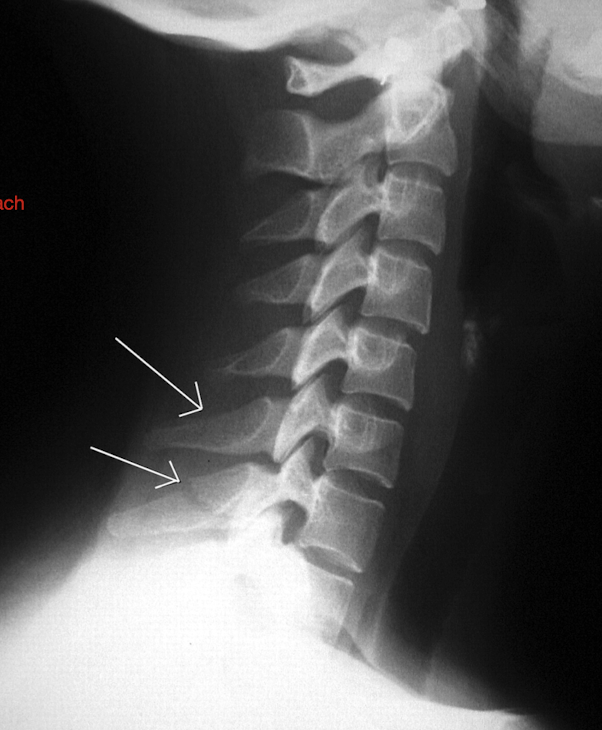

Label these 4 Lines? (C/S)

Notice: Post Vertebrae Intact, Ant Vertebrae w Fx